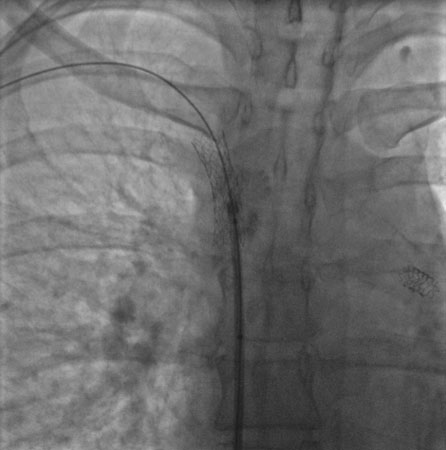

Done percutaneously by obtaining access usually through the femoral vein. Performed under conscious sedation. Fluoroscopic guidance and iodinated contrast are used. Most operators use heparin during the procedure. [Figure caption and citation for the preceding image starts]: Postdilatation of the superior vena cava stentImage obtained from cardiac catheterization laboratory at University of Missouri, Columbia; used with permission [Citation ends].[Figure caption and citation for the preceding image starts]: Venography showing superior vena cava stenosis. Stent placement in the left pulmonary artery is seenImage obtained from cardiac catheterization laboratory at University of Missouri, Columbia; used with permission [Citation ends].

Undertaken percutaneously by obtaining access (usually) through the femoral vein. Performed under conscious sedation. Fluoroscopic guidance and iodinated contrast are used and most operators use heparin during the procedure.[Figure caption and citation for the preceding image starts]: Postdilatation of the superior vena cava stentImage obtained from cardiac catheterization laboratory at University of Missouri, Columbia; used with permission [Citation ends].[Figure caption and citation for the preceding image starts]: Venography showing superior vena cava stenosis. Stent placement in the left pulmonary artery is seenImage obtained from cardiac catheterization laboratory at University of Missouri, Columbia; used with permission [Citation ends].